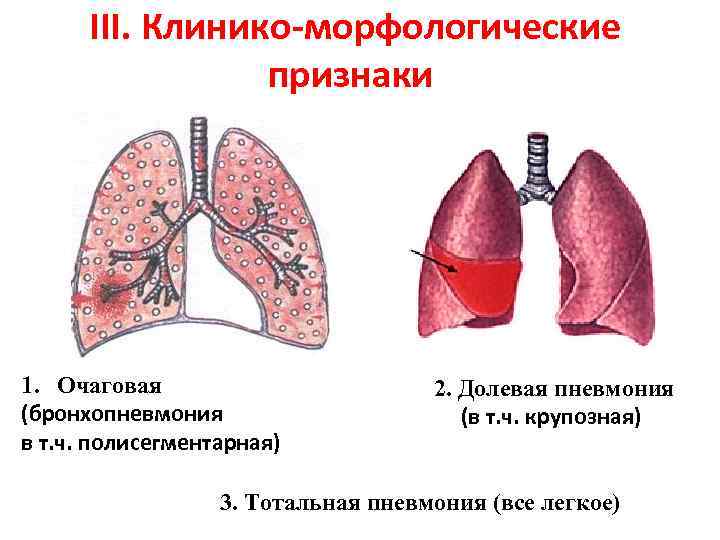

Фотографии бактерий, вызывающих бактериальные пневмонии у животных

Раздел: Другие животные